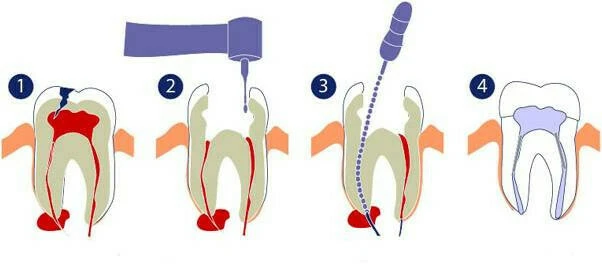

1. Thế nào là sự dịch chuyển ống tủy (Canal transportation)

Hiệp hội nội nha Mỹ định nghĩa sự dịch chuyển ống tủy như sau:

“Sự dịch chuyển ống tủy là việc loại bỏ cấu trúc thành ống tủy bên ngoài đoạn cong ở ½ chóp do các trâm nội nha có khuynh hướng khôi phục lại hình dạng ban đầu của nó trong quá trình sửa soạn ống tủy; điều này có thể dẫn đến việc hình thành khấc và khả năng thủng thành ống tủy.”

Với hợp kim đang được sử dụng, bất kì trâm nội nha nào cũng có khuynh hướng thẳng trở lại bên trong ống tủy. Do đó lực tác dụng của mặt cắt dụng cụ lên phần tiếp xúc với thành ống tủy không đều nhau, dẫn đến việc loại bỏ ngà răng không đồng đều. Trong đó, mặt cắt tác dụng nhiều ở phần cong lồi tại 1/3 chóp và ở phần cong lõm tại 1/3 giữa và 1/3 cổ. Kết quả là mô ngà có khuynh hướng bị lấy đi nhiều ở phần cong lồi tại vùng chóp và ở phần cong lõm tại vùng phía cổ răng của ống tủy, dẫn đến sự dịch chuyển ống tủy hoặc làm thẳng ống tủy.

Hình bên dưới minh họa cho trường hợp sửa soạn bằng trâm K làm bằng thép không rỉ. Hình nảnh ống tủy bị dịch chuyển. Chú ý phần màu hồng là phần mô không được loại bỏ đầy đủ.